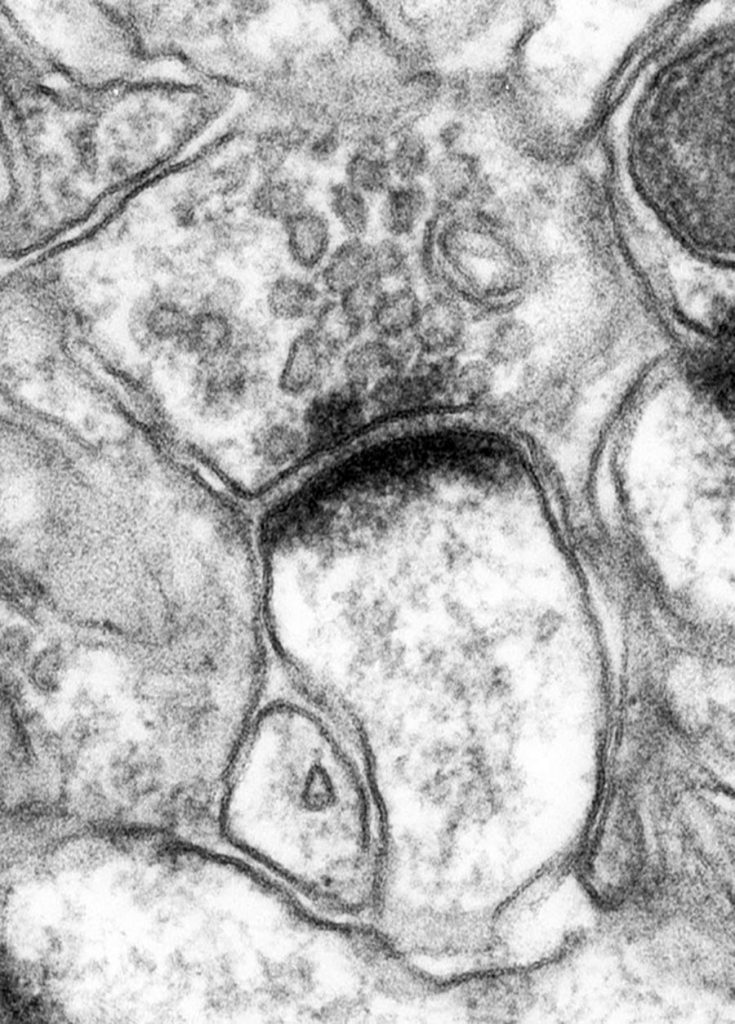

叠加证据表明AD主要是神经元机能失灵并影响神经元相互通信方式帮助驱动我们对AD神经病理变化的理解是西班牙Castilla-LaMancha大学Rafael Lujn教授Lujn使用敏感前沿免疫-电子显微技术并用生化技术调查四大关键蛋白5MPA和GABAB使用AD鼠标模型,他确定这些蛋白质在疾病期间在脑中变换的时间和方式点精确子细胞定位对这些蛋白质功能有重要影响并损及神经元处理和传输信号的基本能力

GIRK通道可能由四个子单元组成(GIRK1、GIRK2、GIRK3、GIRK4),但在脑中这些通道通常由GIRK1和GIRK2子单元组成Luján研究队使用技术挑战式免疫电子显微实验,仔细检查GIRK2通道定位问题,GIRK2通道是神经活动的重要抑制器,在河马院中先发制人GIRK2表示式与控制鼠比大减10个月的P301S小鼠GIRK2通道沿神经元表面及其再分布可能改变金字塔细胞易感性,导致与AD相联的认知功能受损